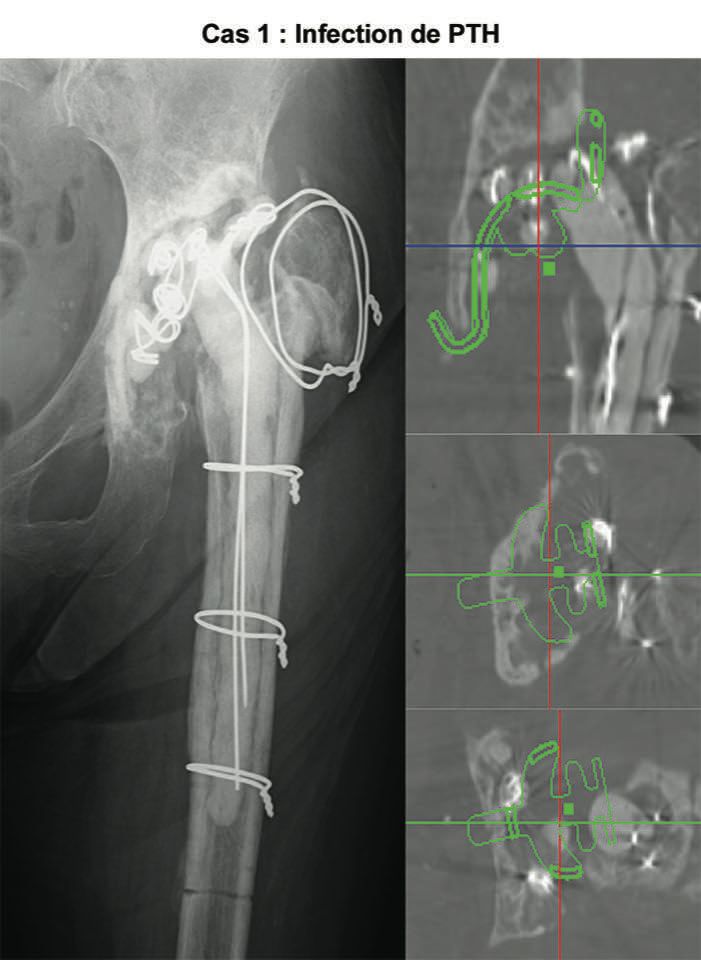

The video demonstrates the technique for reconstructing the acetabulum using an allograft and KT device (Fig. 16). It shows a two-stage revision hip replacement due to an infection. The bone defect was classified during the preoperative planning as AAOS III (combined defect).

Figures 17 and 18 show the preoperative x-rays and 3D CT images. The acetabulum was reconstructed using a KT cross and allografts.

The segmental and cavitary defects were successfully filled. Figures 19 and 20 show the postoperative images.